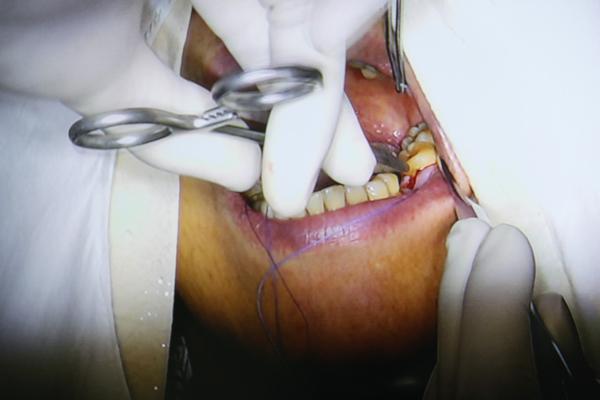

医生将种植体植入牙槽骨中

种好后对种植部位进行缝合

8分钟后,种植手术完成